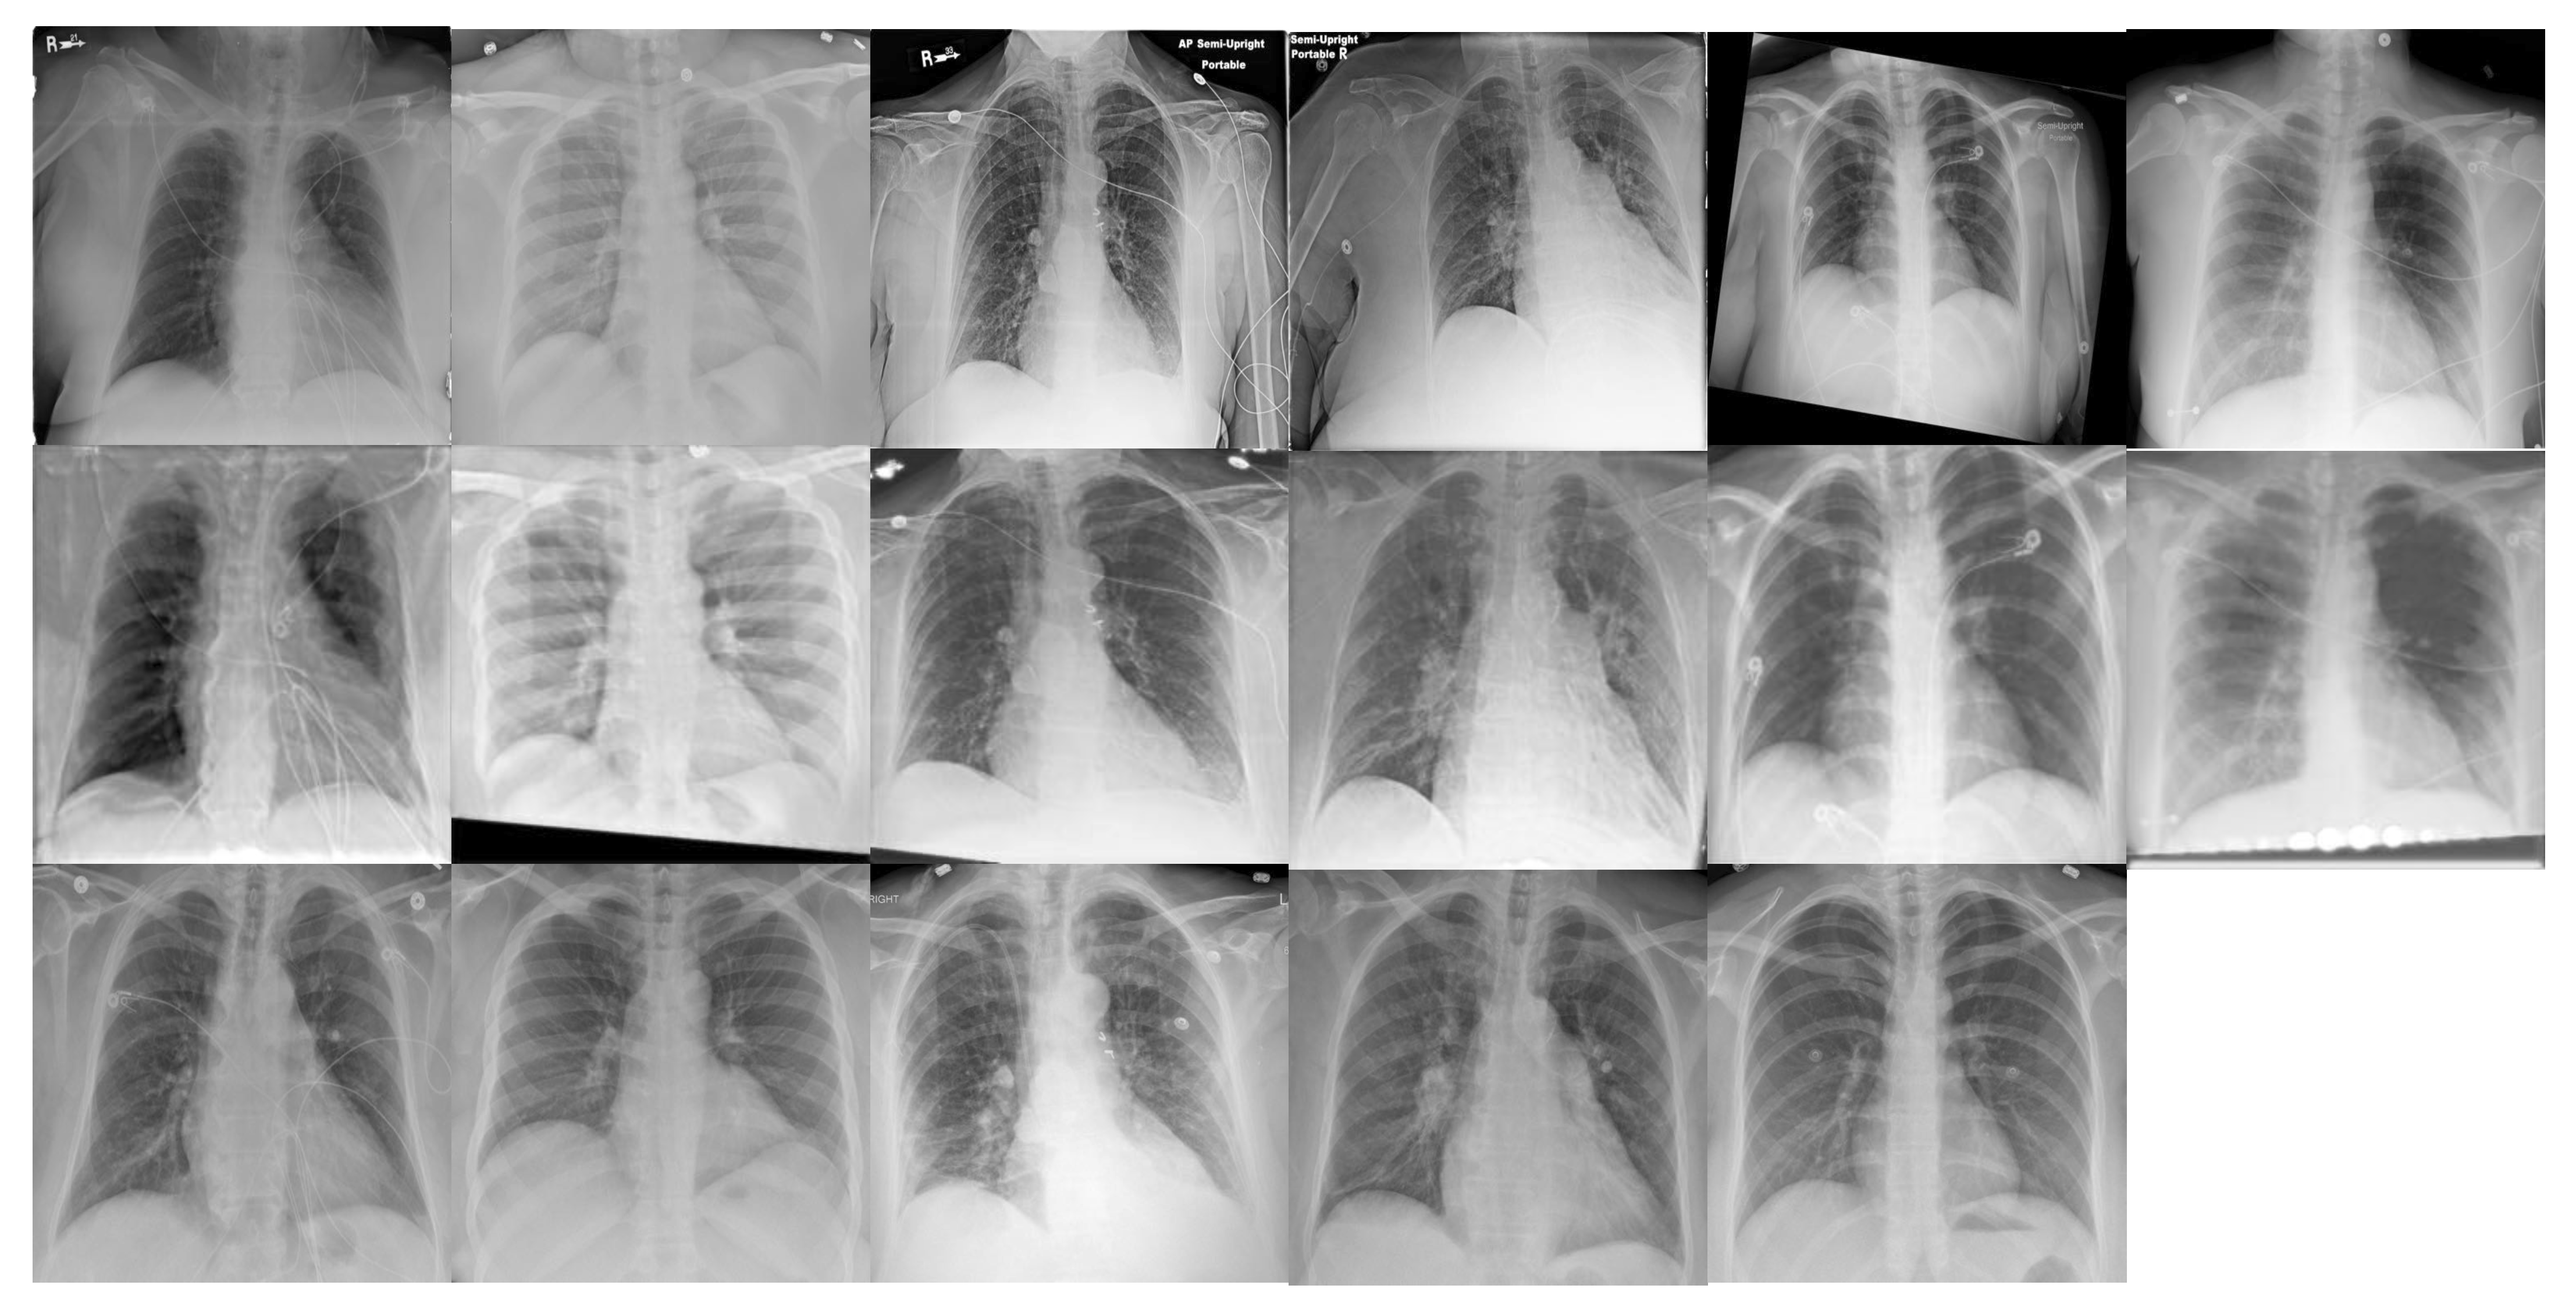

4.1. Database

- Firstly, we introduce a novel database collection of subject-pairs radiographs. For each subject, we collect a pair of samples which are from both portable machines (source domain) and conventional machines (target domain).